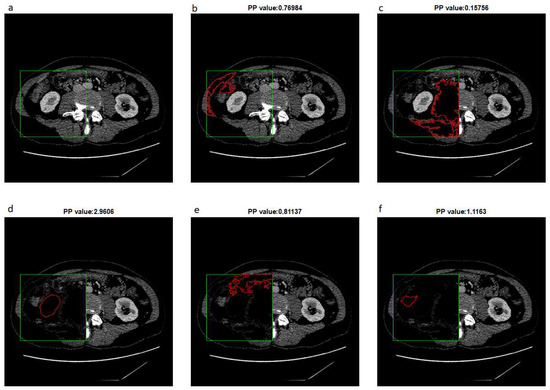

The next step is to leave one result for which s u m P is the highest and fill the holes and denote as H 0 the value of H . In the next step, the extended-maxima transform is executed again but in the raw C t s image. Each time algorithm is executed, the circularity coefficient P P is calculated and the result of the operation is removed from the image. According to this procedure, we generate u number of masks which are potential candidates for the final kidney mask. Finally, the mask of the highest P P value is selected. The result of the next five steps is shown in Figure 3.

Figure 3. The result of the next five steps of extended-maxima transforms and result in removing. For example, (a) is an original image, and examples (bf) show different shapes found in the next steps. The result of the operation is removed from the image after each step. The circularity factor P P is calculated for each result.